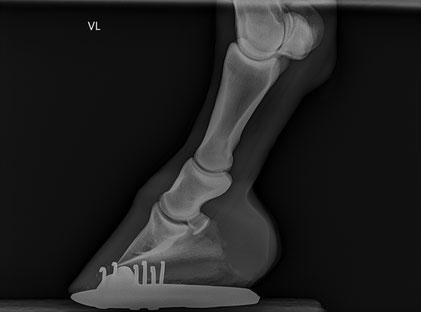

• Röntgenuntersuchung (nach aktuellem Röntgenleitfaden 2018 der Bundestierärztekammer / GPM)

• 2 × Oxspring-Aufnahme (Strahlbeine/Hufrolle)

• 2 × Huf seitlich (90°)

• 2 × Zehe seitlich (Fesselgelenk, 90°)